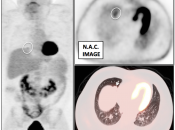

Value of Non-Attenuation Corrected (NAC) Images

Resolving Attenuation Correction Artifacts:

The CT images obtained during an exam are not only used for “anatomic” interpretation. They are also used for “attenuation correction” (AC) of the PET images, generating the much more useful AC PET images used for interpretation.

Unfortunately, attenuation correction of PET images can result in falsely elevated metabolic activity in regions of high CT density (e.g. metallic devices, oral contrast, calcification).

In such cases, these areas must be reviewed on the NAC (non-attenuation correction) images. If these regions are not also hypermetabolic on the NAC images, then their apparent increased FDG-uptake on the AC images is artefactual.

This phenomenon is almost exclusively seen with older PET/CT scanners, as most modern scanners utilize newer algorithms that do not “over-correct” in these areas of increased density.